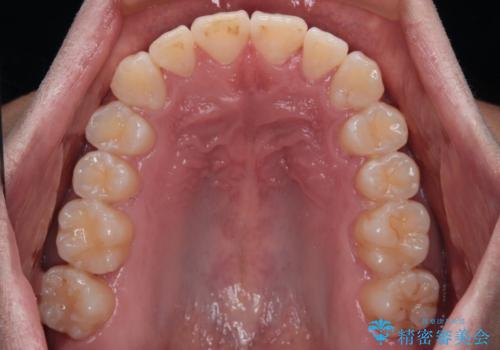

- 前歯のデコボコを治したいとのことで来院された患者様です。

上下顎ともに歯列全体の後方移動とIPR(歯と歯の間を削る)によってデコボコが解消するように設計し、インビザラインにより治療を行うこととしました。